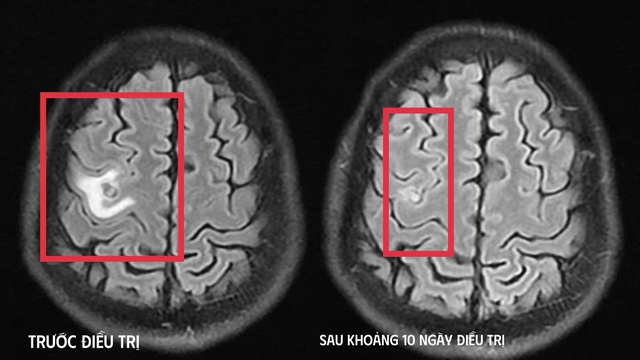

Hình ảnh chụp chiếu trước và sau khi điều trị (Ảnh: BVCC).

Sau khoảng 10 ngày điều trị nội trú, tình trạng bệnh cải thiện rõ rệt như hết tê tay, không còn cơn co giật, không đau đầu hay chóng mặt, toàn trạng ổn định. Người bệnh được cho ra viện và tiếp tục điều trị ngoại trú đủ liệu trình kéo dài 4 tuần.

Khi tái khám gần một tháng sau, phim MRI cho thấy tổn thương não thu nhỏ rõ rệt, phù não giảm, không còn dấu hiệu tiến triển, chứng tỏ đáp ứng điều trị tốt. Bệnh nhân được chỉ định thêm một đợt thuốc củng cố và theo dõi lâu dài.